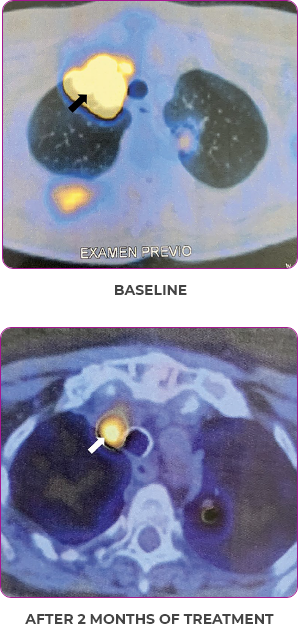

Response in primary and metastatic lesions1

Lung imaging of primary tumors.

SCAN 1: LUNG

SCAN 2: LUNG AND BONE

Images courtesy of Dr Maximilian Hochmair.

Response to VITRAKVI1

- Partial response and symptom improvement confirmed by chest X-rays after <1 month of treatment

- Imaging performed 6 weeks into treatment revealed considerable decrease in the size of both target lesions

- No treatment-related AEsa were reported

- Complete clinical response achieved by 12 months with residual scarring

- Patient was symptom free and remained on VITRAKVI